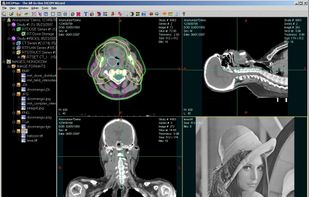

All-In-One DICOM Wizard for Radiation Oncology and Radiology. DICOMan is a DICOM/DICOM-RT viewer enhanced with a set of built-in tools such as DICOM Decompressor, DICOM Pusher, DICOM Retriever, DICOM Editor, DICOM Anonymizer, DICOM Format Converter and so on. DICOMan is such a s.